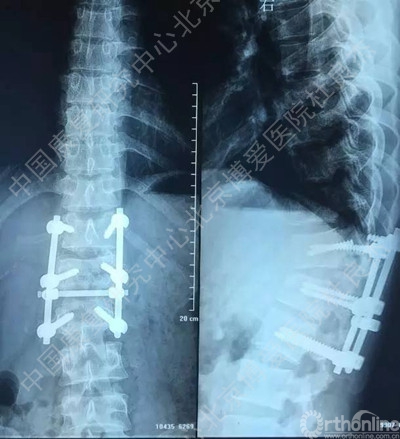

一月前干活时腰背部不慎被重约1吨重物砸伤,当时无意识障碍,无恶心、呕吐症状,自觉腰背部剧烈疼痛伴胸闷、憋气,双下肢失去知觉并不能活动,被送到当地医院救治,当时影像学检查示“腰1爆裂骨折伴脱位,腰1椎体附件骨折,腰2右侧横突骨折,胸12腰1之间侧方脱位,右侧第12肋椎关节脱位,右侧气胸,双肺挫伤,双侧胸腔积液”,经全面检查后诊断“胸12腰1骨折脱位,脊髓不全损伤,腰1椎体附件骨折,腰2右侧横突骨折,右侧第12肋椎关节脱位,右侧气胸,双肺挫伤,双侧胸腔积液等”。

伤后当天在全麻下行“后路探查减压复位椎弓根钉内固定植骨融合术”。手术后给予综合治疗,患者双下肢肌力较术前好转,但仍存在无力及感觉异常,大小便功能无明显改善。为进一步康复治疗及训练就诊中国康复研究中心北京博爱医院,以“腰椎骨折术后并脊髓损伤”收住院。患者近期精神、饮食、睡眠好,小便留置尿管,大便需借助开塞露。

手术后辅助检查

3、胸12椎弓根钉断裂